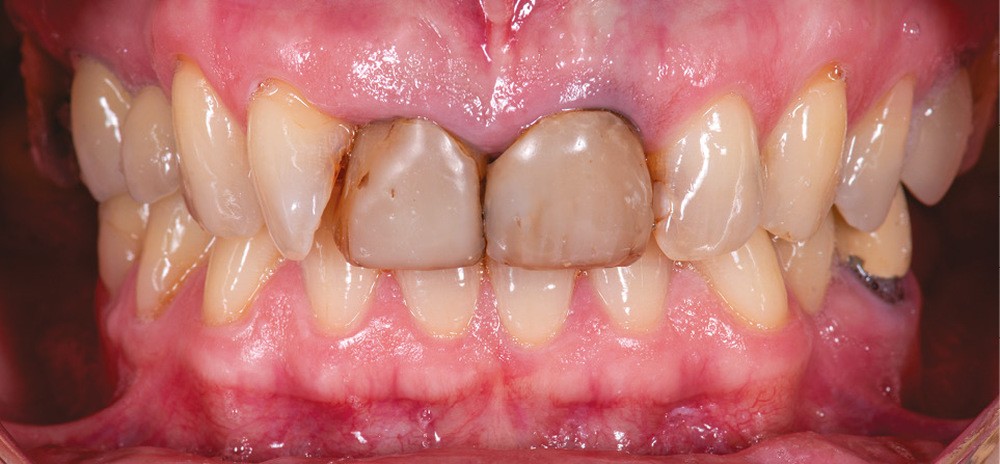

Présentation du cas (fig. 1 et 2)

Une patiente de 55 ans se présente pour une prise en charge esthétique de son sourire. Sa demande regroupe à la fois la teinte, l’encombrement incisivo-canin et l’asymétrie des incisives centrales.

Les deux incisives centrales ont été traitées endodontiquement plusieurs années auparavant et restaurées par des composites directs.

Le contrôle de plaque est insuffisant et nous notons une perte d’attache entre 12 et 11.

La patiente refuse d’emblée tout traitement orthodontique, même par aligneurs.